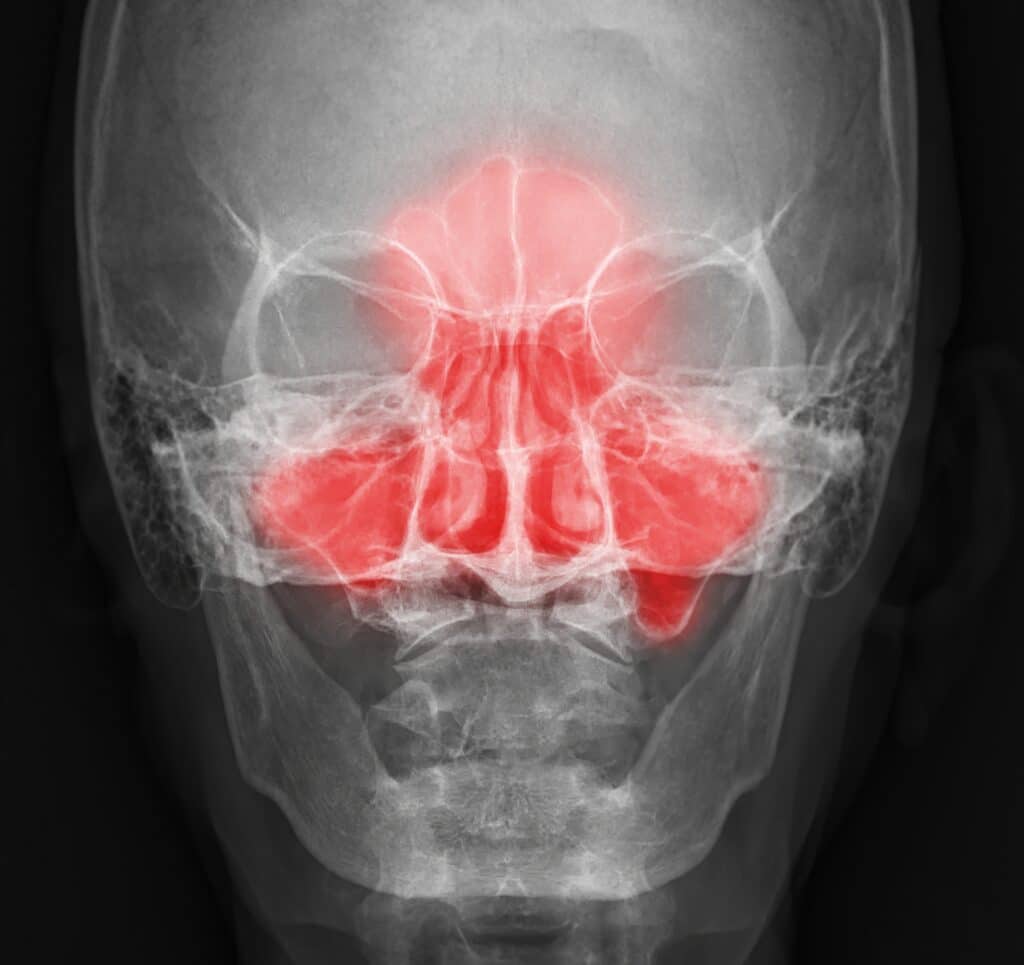

Dagmar klinikken råder over sofistikeret navigationsudstyr og 4K billeddannende teknologi og besidder en meget høj grad af specialisering hvad angår enhver form for kirurgi i bihulerne. En operation for næsepolypper eller for at afhjælpe gentagne bihulebetændelser udføres med kikkert gennem dine næsebor og efterlader altså ingen synlige ar.